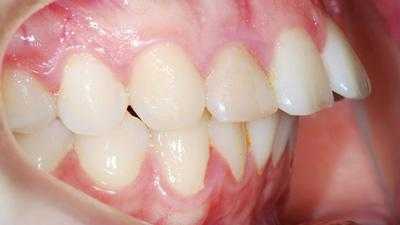

Внутриротовые признаки

В полости рта дистальный прикус определяется по выступающим вперед верхним фронтальным зубам. В норме, при ортогнатическом прикусе, верхние резцы перекрывают нижние примерно на 1/3. При дистальной патологии между верхними и нижними резцами образуется расстояние — «саггитальная щель».

- II подкласс — передние зубы растут по направлению назад, смыкаются с нижними резцами, саггитальная щель отсутствует.